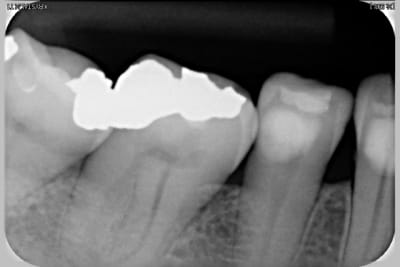

Radio 36 2009 liviaq - Eugenol

Radio 16 2009 alhcqr - Eugenol

Radio 25 2009 pd2mbc - Eugenol

Radio 46 2009 eomewu - Eugenol

Voir images

On peut y voir une remodelage osseux, de tartre, l'usure de la canine